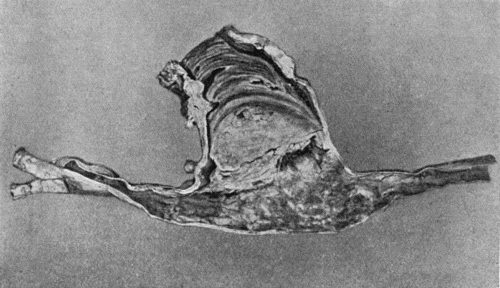

108.Avulsion of Tendon 410

109.Volkmann's Ischæmic Contracture 414